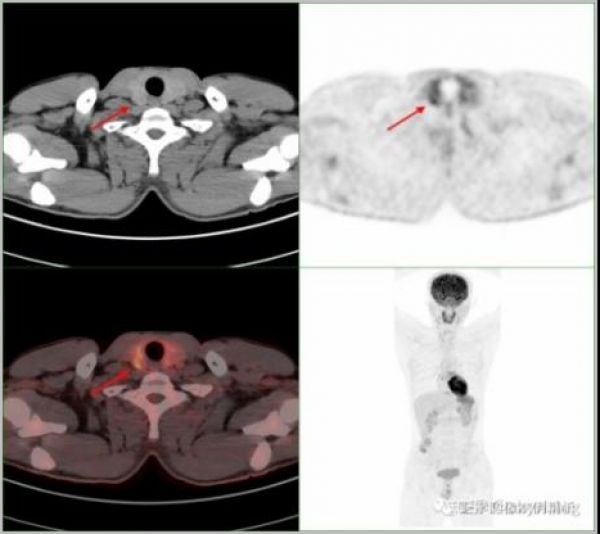

核医学PET/CT检查

荆门市中心医院目前配备的PET/CT设备,不仅能鉴别肺部结节性质,还适用于全身多种肿瘤的早期探测,为肿瘤高危人群(如长期吸烟者、有肿瘤家族史、肿瘤标志物异常者等)、肿瘤定性与鉴别诊断、肿瘤分期、肿瘤疗效评价等方面提供了可靠的健康守护。在这里,每一次精准的检查,都是对生命的郑重承诺;每一次及时的诊断,都在为健康争取更多可能。